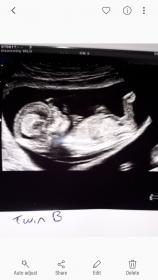

So I had my scan today and confirmed twins, no nub pic from baby A but didn't see anything that screamed boy to me but this is, what I think is a nub, from baby b, am I right in thinking this is likely to be a boy? Thanks.

I don't see any clear gender clues in your pic- that cute little leg is covering the nub area.

Wouldn't you think that bright white line is nub? As I thought it was and it looks angled to me. Maybe I'm out of touch lol.

The pic is quite small but I zoomed in and I think what I see is nub, not sure as it's not clear. It looks maybe girly but I'm not confident. I do get girly vibes overall though. Hope I'm right!

Not sure if this pic is any better :-)

Slight girl lean but that little leg is in the way.

See I thought that would defo be a boy as the line looks angled to me lol not sure I know what I'm looking at anymore lol. Thanks for your guess :-)